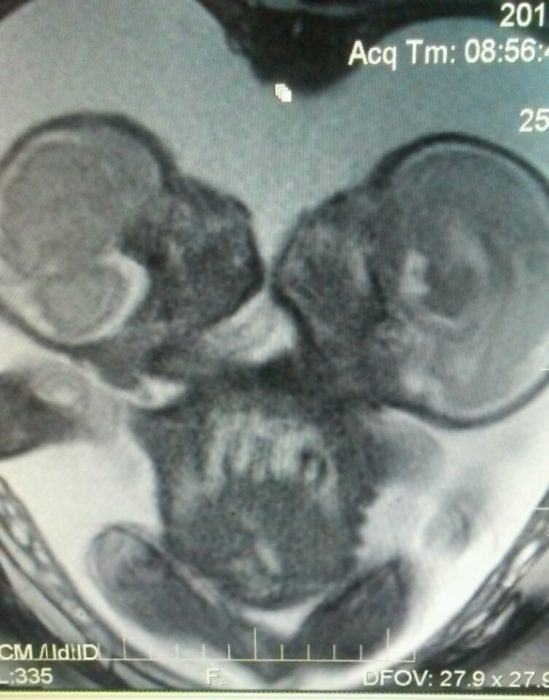

A North Carolina couple, after choosing life and saying abortion was not an option for them, are now the parents of seven children after giving birth to conjoined twins. Jason and Heather Kroeger were already the parents of five children when Heather realized she was pregnant. At first, the happy couple thought they only had one baby on the way — but a follow-up ultrasound revealed that they not only were expecting twins, but that they were conjoined.

Elijah and Isaac were born September 5th, a miracle in and of itself, as roughly half of conjoined twins are stillborn. Another 35% die within 24 hours of being born. But the Kroeger twins are alive and thriving, remaining alert, cooing, smiling, and love being held, the GoFundMe page reported.

Unfortunately, Jason explained that his sons cannot be separated, as they share vital organs. But they call the boys a “blessing for the entire family,” and noted that the boys already have distinct personalities. “Isaac’s kind of mellow and calm, and Elijah’s just grabbing and looking around and wanting to touch everything,” he said. “It’s going to be interesting, seeing them grow up and seeing the different personalities between the two.” And while the boys can’t be separated, their condition is better than their medical staff expected it would be.